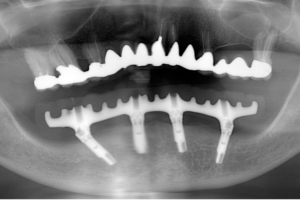

まずは、レントゲン写真をご覧ください。左が1年前、右が先日のものです。ほとんど変わらないですね。特に注目して頂きたいのが、インプラントの周囲の骨です。全く変化なしと言えます。